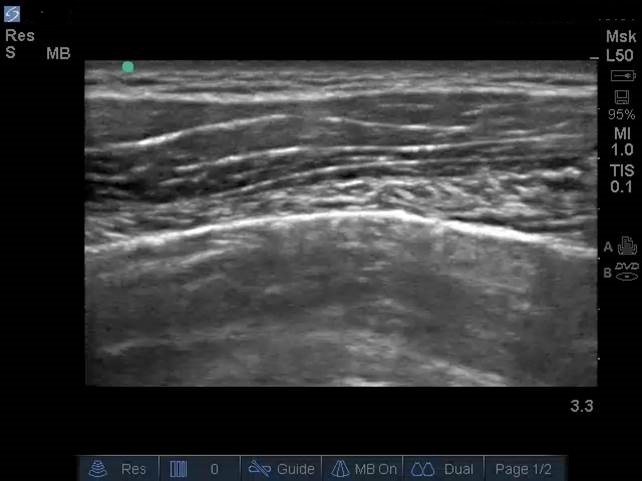

Lung Sliding Image